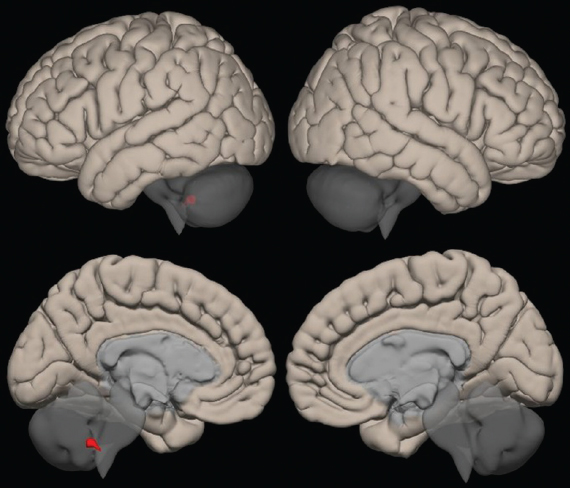

При оценке 1-го и 2-го кластеров сенсомоторной нейросети отмечается увеличение функциональной коннективности в области лобных долей (рис. 4, 5).

Рис. 4. Кластер № 1 сенсомоторной нейросети

Fig. 4. Cluster N 1 of the sensorimotor neural network

Обнаружено повышение функциональной коннективности в левой височной доле (рис. 6), особое внимание обращает на себя тот факт, что изменение функциональной коннективности происходит в сером веществе и площадь увеличения активности довольно большая.

Рис. 6. Кластер № 3 сенсомоторной нейросети

Fig. 6. Cluster N 3 of the sensorimotor neural network

При оценке кластера № 4 (рис. 7) отмечается увеличение функциональной коннективности в угловой извилине. Угловая извилина — регион головного мозга, лежащий в основном в антеролатеральном регионе теменной доли. Ее значение связано с передачей визуальной информации в область Вернике для усвоения письменной речи.

Рис. 7. Кластер № 4 сенсомоторной нейросети

Fig. 7. Cluster N 4 of the sensorimotor neural network

Сенсомоторная нейросеть также показала положительный прирост функциональной коннективности как в областях собственных структур, так и в области лобных долей и височной доли слева (все пациенты — правши), что позволяет предположить, что у пациентов повышается контроль за собственными движениями и восстанавливаются области, которые ответственны за получение двигательных навыков.